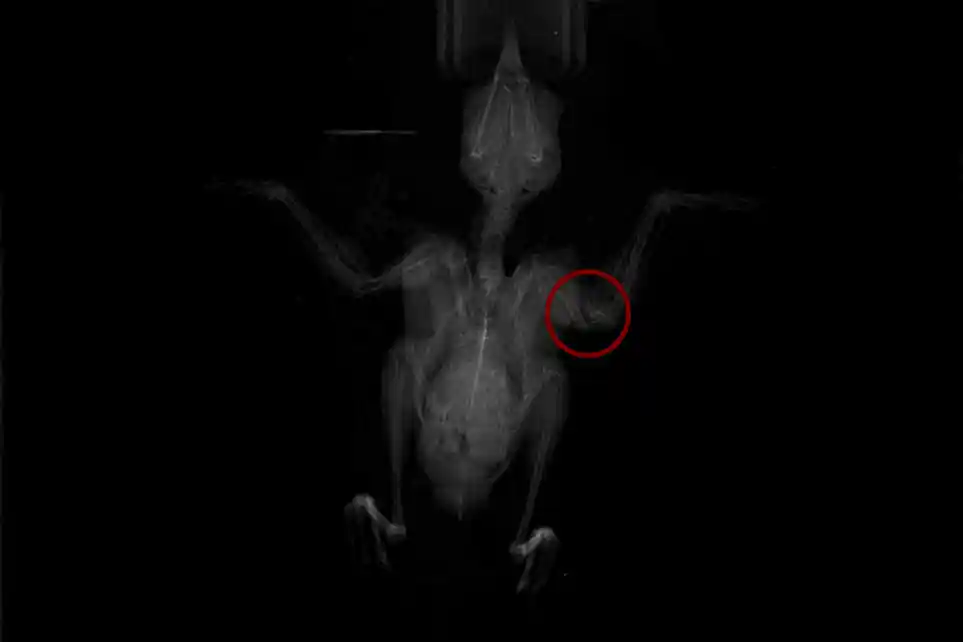

Arriving at the centre after being caught by a cat, this poor great tit was left with a horrific open fracture to the left humerus (the bone between the shoulder and elbow). No longer able to fly, emergency surgery was the only option to give it a second chance at life.

Amazingly, with the bird anaesthetised, Meriem (one of our vets) was able to carefully pin everything back into place using a modified hypodermic needle (a method known as an intramedullary pin, or IM pin) before closing the open wound. These procedures need a very steady hand and keen eyesight, but we’re delighted to say that everything has worked perfectly!

The bone has now healed well and flight has already been restored! Hopefully, it won’t be long before this luttle bird can get back to the skies at last!